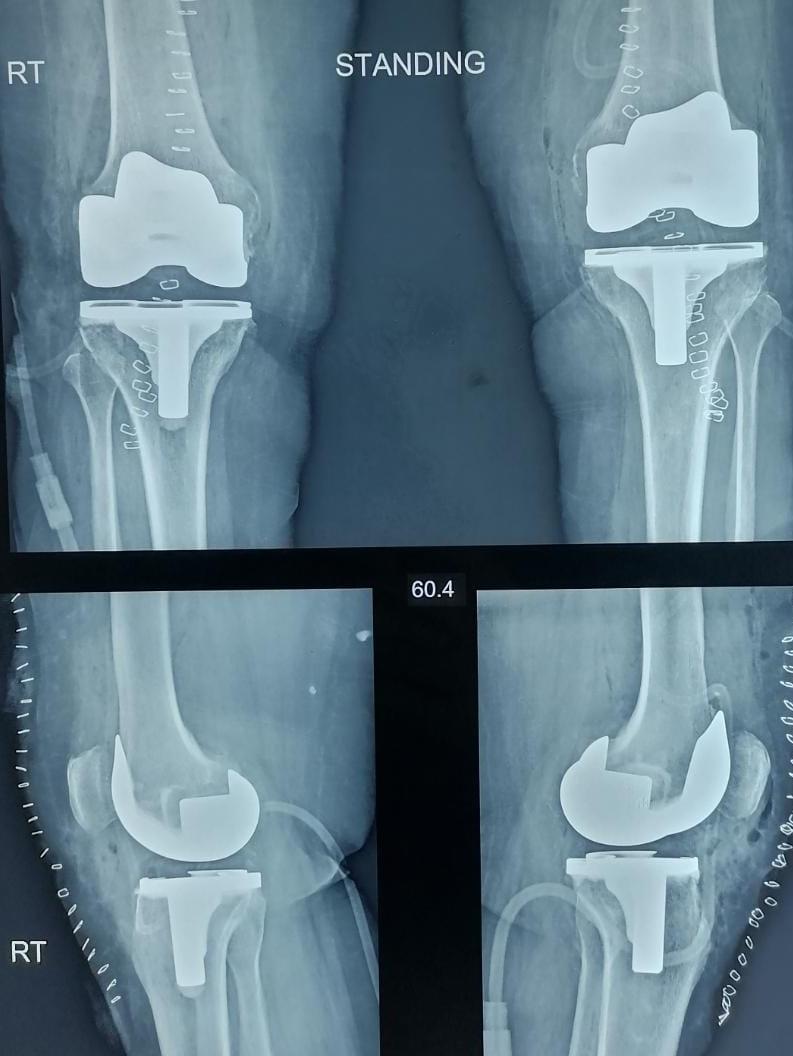

X-ray

Warning: Graphic Content

The following section contains graphic images of surgical procedures. These images are intended for educational purposes and may be disturbing to some viewers. Viewer discretion is advised.

Surgeries